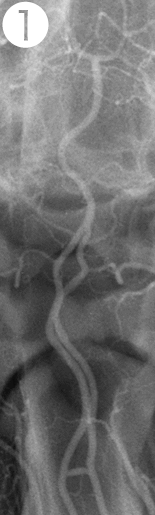

モデル動物の脳血管に原因物質SPCを投与して検証

①SPC投与前の血管

⇒正常な血管の状態

②SPC投与2時間後の血管

⇒SPCを一回投与しただけで2時間もの長い間

広範囲で著明な血管の異常収縮が認められた